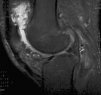

Fig. 1. Resonancia magnética nuclear (RMN) que muestra edema óseo reactivo y moderado derrame articular.